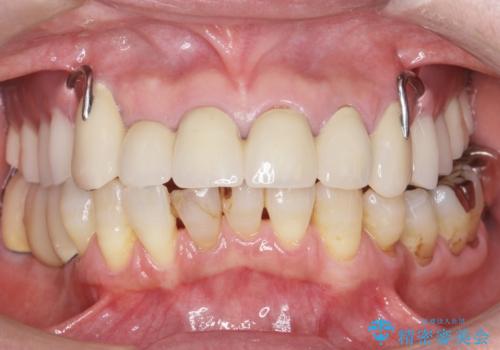

- 下の前歯が欠けてぐらぐらすることを主訴に来院された患者様です。

4年前に行った他の部位の治療にご満足頂け、再来院して下さいました。(こちらの症例です→ https://seimitsushinbi.jp/case/68066/ )

以前行った奥歯の治療により下顎前歯の動揺は改善傾向にあり顕著ではなかったのですが、欠けて黒くなっていることと少しの動揺が気になるとのことでした。

元気なうちに治療しておきたいという患者様の強いご希望により、下顎前歯の連結補綴と欠けている小臼歯の補綴治療を行いました。

自然な仕上がりに喜んで下さいました。

クラウンを連結することにより気にされていた動揺もなくなり、安心して頂けました。

被せ物の種類:オールセラミッククラウン スタンダード